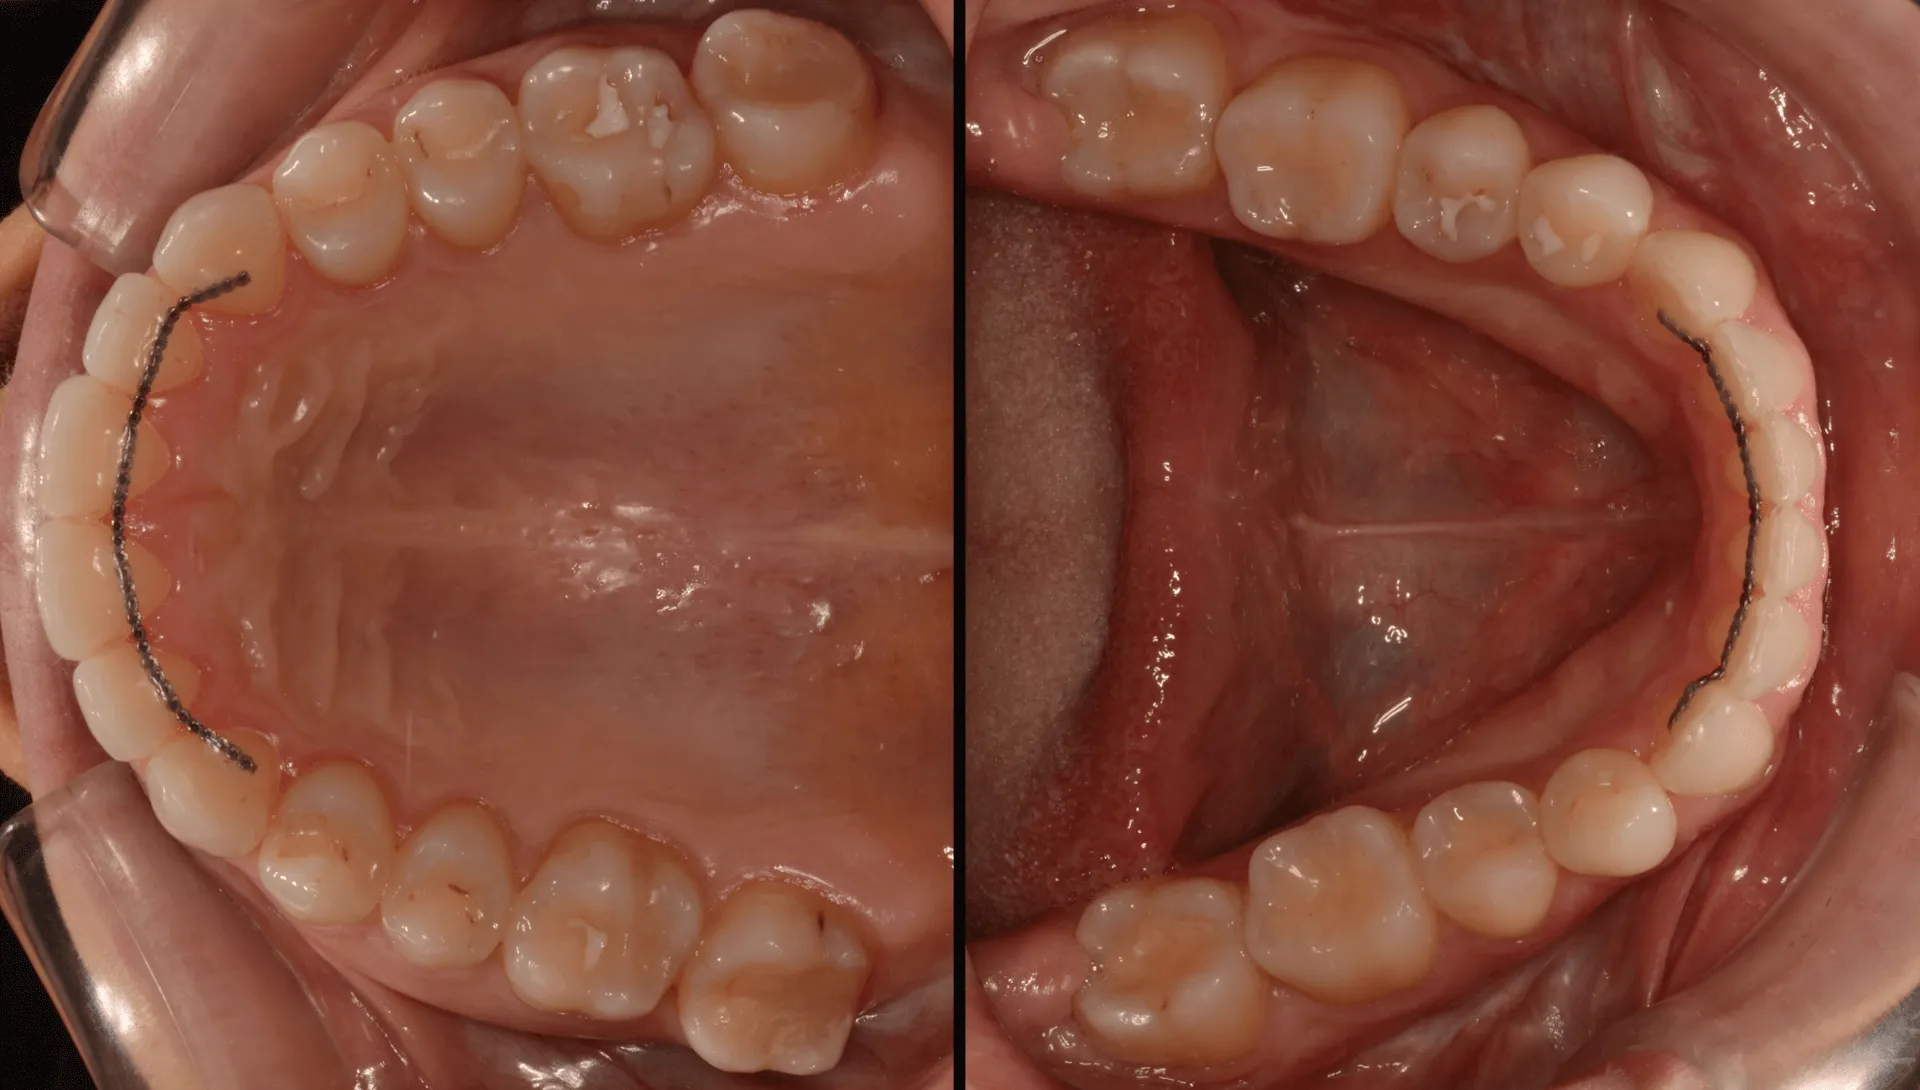

At our Center we use cutting-edge tools to plan your treatment with the highest accuracy. We’ll capture high-quality photos, intraoral scans and face scans, use 3D or 2D X-rays and establish a thorough TMJ diagnosis with Modjaw and MRI — as needed. These create a 3D Dental Avatar — a virtual 3D face model — helping us plan your treatment — customized just for you.

Your custom-made aligners are ready to start your smile transformation! If needed, we’ll gently bond small attachments or accessory elements to your teeth to enhance precision. Wear your aligners for 20-22 hours daily, and switch to a fresh set every 1-2 weeks as guided. We’ll ensure the perfect fit and confirm your teeth are shifting beautifully on schedule every 6-8 weeks. After your final aligner, we’ll schedule a visit for a thorough exam and intraoral scan to verify your stunning results. If tiny adjustments are needed, we’ll provide extra aligners — the perfect result is our priority!

Your smile is an investment and we’re here to protect it — so after removing the attachments and accessory elements – if they were needed – and also polishing your teeth, we’ll provide you retainers: a fixed wire bonded behind your front teeth and a removable splint for nighttime wear. We’ll teach you how to care for them and take final photos and scans to showcase your transformation. We’ll also discuss the checkups to maintain your results long-term.